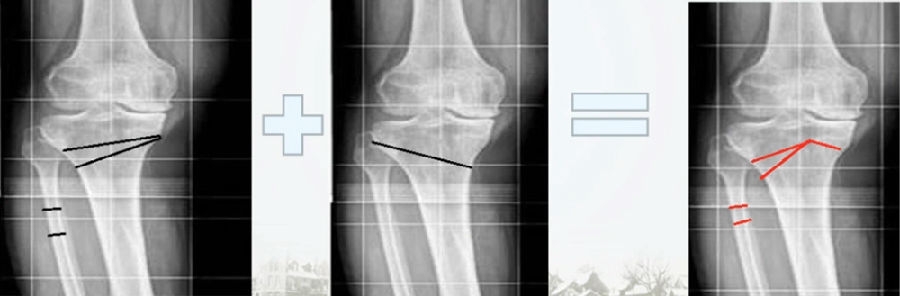

典型病例,男性,65岁,农民,双膝内翻16度。

术前影像

第一次为该患者做了传统上行开放截骨,撑开角度较大,术后用三种方法测量髌骨高度,发现髌骨高度受到影响,髌骨变低了。

左膝上行OWHTO(初次)

上行OWHTO髌骨高度测量

ISI法测量髌骨无明显变化;CDI、BPI法测量髌骨降低明显;患者屈膝锻炼困难。

第二次来院做另一侧肢体时,采用下行截骨,术后患者髌骨高度,无论用哪种方法测量都无明显变化,而且患者膝关节功能迅速得到恢复。

右膝下行OWHTO(再次)

下行OWHTO髌骨高度测量

ISI法测量髌骨无明显变化;CDI、BPI法测量髌骨无明显变化;患者屈膝明显改善。